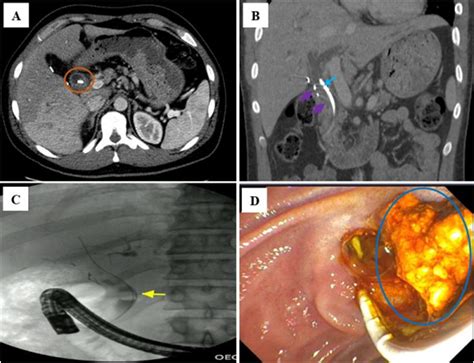

These devices are primarily inserted via a procedure known as Endoscopic Retrograde Cholangiopancreatography (ERCP). During this minimally invasive procedure, a gastroenterologist uses an endoscope—a flexible, lighted tube with a camera—to navigate through the esophagus and stomach into the small intestine, reaching the opening of the bile duct to deploy the stent.

• Imaging: Using fluoroscopy (real-time X-ray), the doctor identifies the exact location of the blockage.

• Deployment: Once the location is identified, the stent is advanced through the endoscope and expanded within the narrowed area of the bile duct.